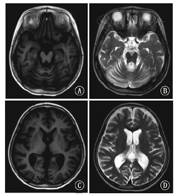

30例患儿均有脑萎缩,其中表现大脑皮质及小脑弥散性萎缩14例(图1),仅有小脑萎缩6例,弥散性脑萎缩伴侧脑室旁白质T2W高信号10例,2例伴双侧内囊后肢T2W高信号,1例伴大脑角T2W高信号。

注:NCL:神经元蜡样质脂褐质沉积症;MRI:头颅磁共振成像;T1WI(A、C)和T2WI(B、D)均可见弥散性脑萎缩 NCL:neuronal ceroid lipofuscinosis;MRI:magnetic resonance imaging;diffuse brain atrophy was observed on both T1WI (A,C) and T2WI (B,D)